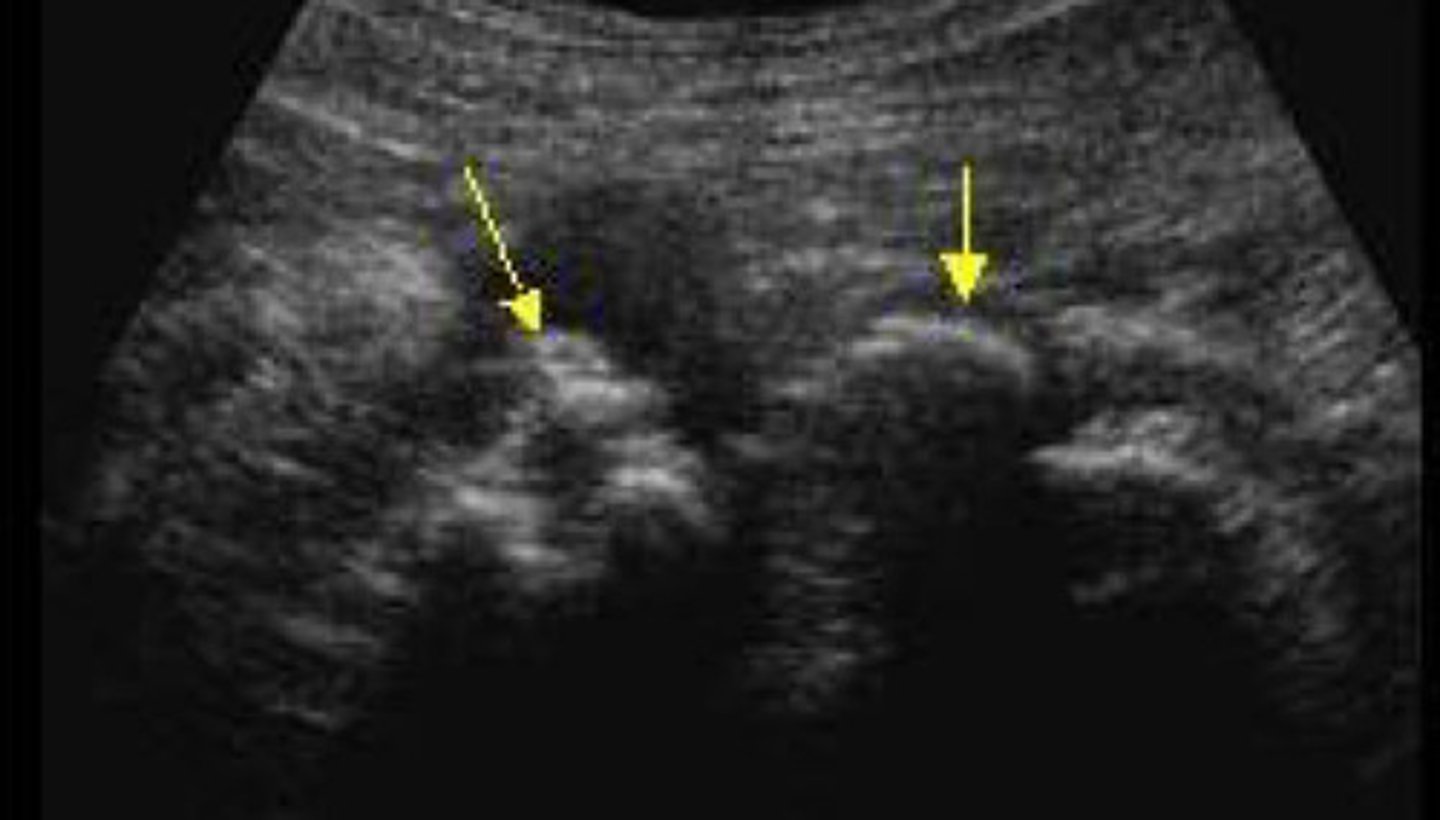

Nephrolithiasis

What does this image show

Twinkle artifact

What is an artifact that a stone may produce

When a stone is located in the sinus region, it is hard to determine if it is a stone bc it will blend into the hyperechoic sinus. You can use colour or power Doppler to look for a twinkly artifact a stone will give off

Explain how you can use the twinkling artifact to your advantage when suspicious of a stone in the sinus region

Stone difficult to identify in the sinus region

Stone now identified with the twinkle artifact

Colour reverberation

What is the twinkling artifact

Colour or power Doppler

What mode do you have to use in order to be able to see the twinkling artifact